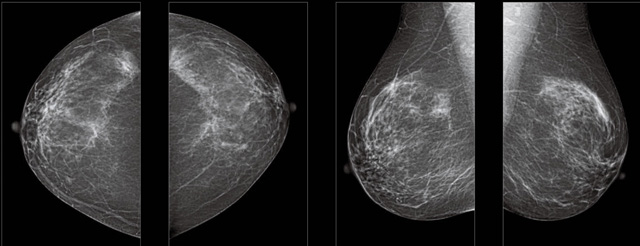

首先不同年齡階段的乳腺篩查頻次種類不一樣。青春期女性第二性征明顯發(fā)育開始,每個月進(jìn)行自我乳腺檢查。20-30歲的女性就不推薦進(jìn)行乳腺檢查,因為年輕女性的乳腺組織非常緊急。鉬靶X光線等檢查的射線不能辨別腫塊跟腺體。身體就白吸收了輻射,影響了身體健康。每個月自檢一次就是在洗澡時候,對著鏡子看看乳房外觀正常,皮膚潰爛、腫塊、顏色改變、再摸一下有沒小疙瘩。乳腺高危人群,特別是有乳腺CA遺傳傾向的女性,乳腺導(dǎo)管跟小葉不典型增生,原位癌。30歲前有乳房放療的女性。乳腺癌篩查可以把年齡提前到40歲前。40到70歲的女性可以在適合的機會篩查。

采用影像檢查技術(shù)來發(fā)現(xiàn)疑似特定病檢查跟人群的普查。一到兩年進(jìn)行一次X光線的乳腺檢查。記過是C或者D型,可以加上B超協(xié)同。還可以一年一次核磁共振MRI檢查。70歲以上的女性認(rèn)為絕經(jīng)的女性是比較安全的。實際上也有乳腺癌的風(fēng)險。65歲以上風(fēng)險也很大。也是需要進(jìn)行機會性篩查。